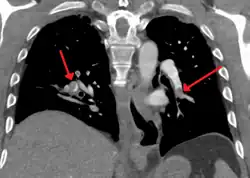

Example of a CTPA, demonstrating a saddle embolus. The white area above the center is the pulmonary artery, opacified by radiocontrast. Inside it, the grey matter is blood clot. The black areas on either side are the lungs, with around it the chest wall.

A normal CTPA scan will show the contrast filling the pulmonary vessels, appearing as bright white. Any mass filling defects, such as an embolus, will appear dark in place of the contrast, filling/blocking the space where blood should be flowing into the lungs.

On CTPA, the pulmonary vessels are filled with contrast, and appear white. Any mass filling defects (embolus or other matter such as fat) appears darker. Ideally, the scan should be complete before the contrast reaches the left side of the heart and the aorta, as this may mean contrast has drained from the pulmonary arteries, or require a larger dose of contrast media.[12]